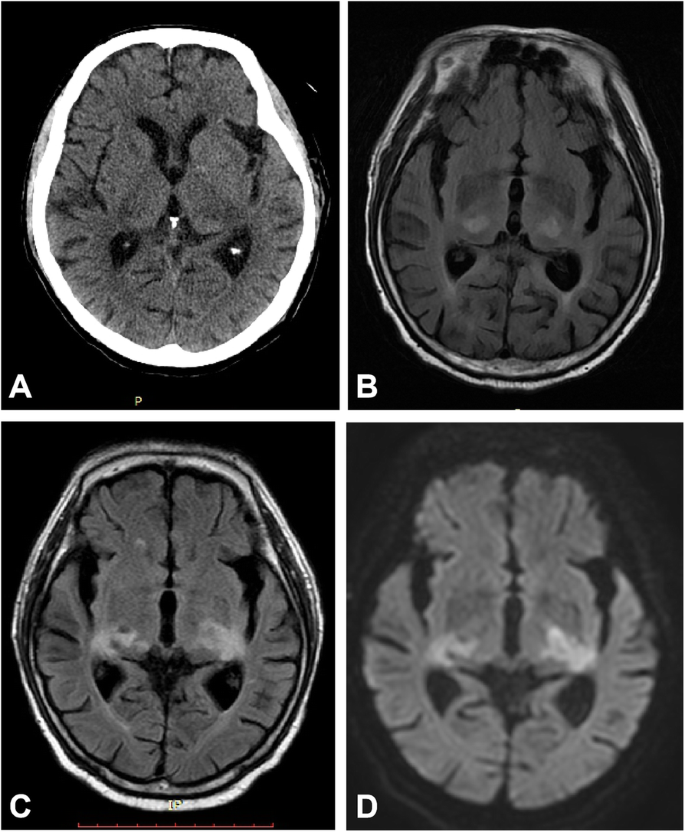

Magnetic resonance imaging (MRI) of the brain on the night of hospitalization demonstrated focal symmetrical bilateral lesions in the thalamus with hyperintense T2 and fluid-attenuated inversion recovery (FLAIR). A head MRI after 17 days showed enlargement of the bilateral thalamic lesions with low density changes in computed tomography. The diffusion-weighted images (DWI) showed a slightly high intensity (Fig. 1). No evidence was found of signal changes in the deep cerebral veins or the straight sinus. There were also progressive multiple lesions in the subcortical white matter, brain stem and a hyperintense long segment of T2 in the thoracic spinal cord. The cranio-cervical computerized tomography angiography (CTA) was unremarkable. (Supplementary materials).

CT and MRI scans showing bilateral thalamic lesions. The CT scan of the head shows low density changes in the bilateral thalamic lesions (a). Axial FLAIR image reveals symmetric hyperintense signal alterations in thalami (b) and enlargement of the lesions after 17 days (c) with mild hyperintensity changes in DWI (d)